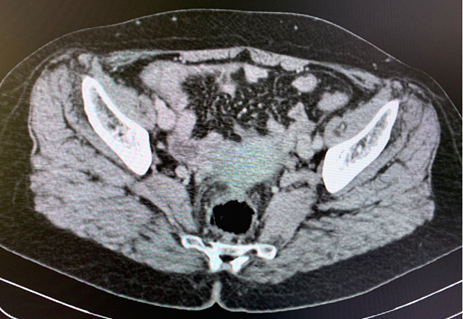

The abdomino-pelvic scanner showed peritoneal carcinomatosis secondary to a right ovarian mass without digestive thickening or deep adenopathy and without bone abnormalities. We completed with pelvic ultrasound showing a par-uterine mass measuring 81 mm with great abundance effusion.

The patient received first line chemotherapy based on carboplatin and paclitaxel. After 6 cures she obtained a partial clinical, biological and radiological response (Fgure 1).

The metastatic lesions appear hyper vascularized on the abdominal injected CT scan. In the present case, hypervascularization was objectived with gallstones.